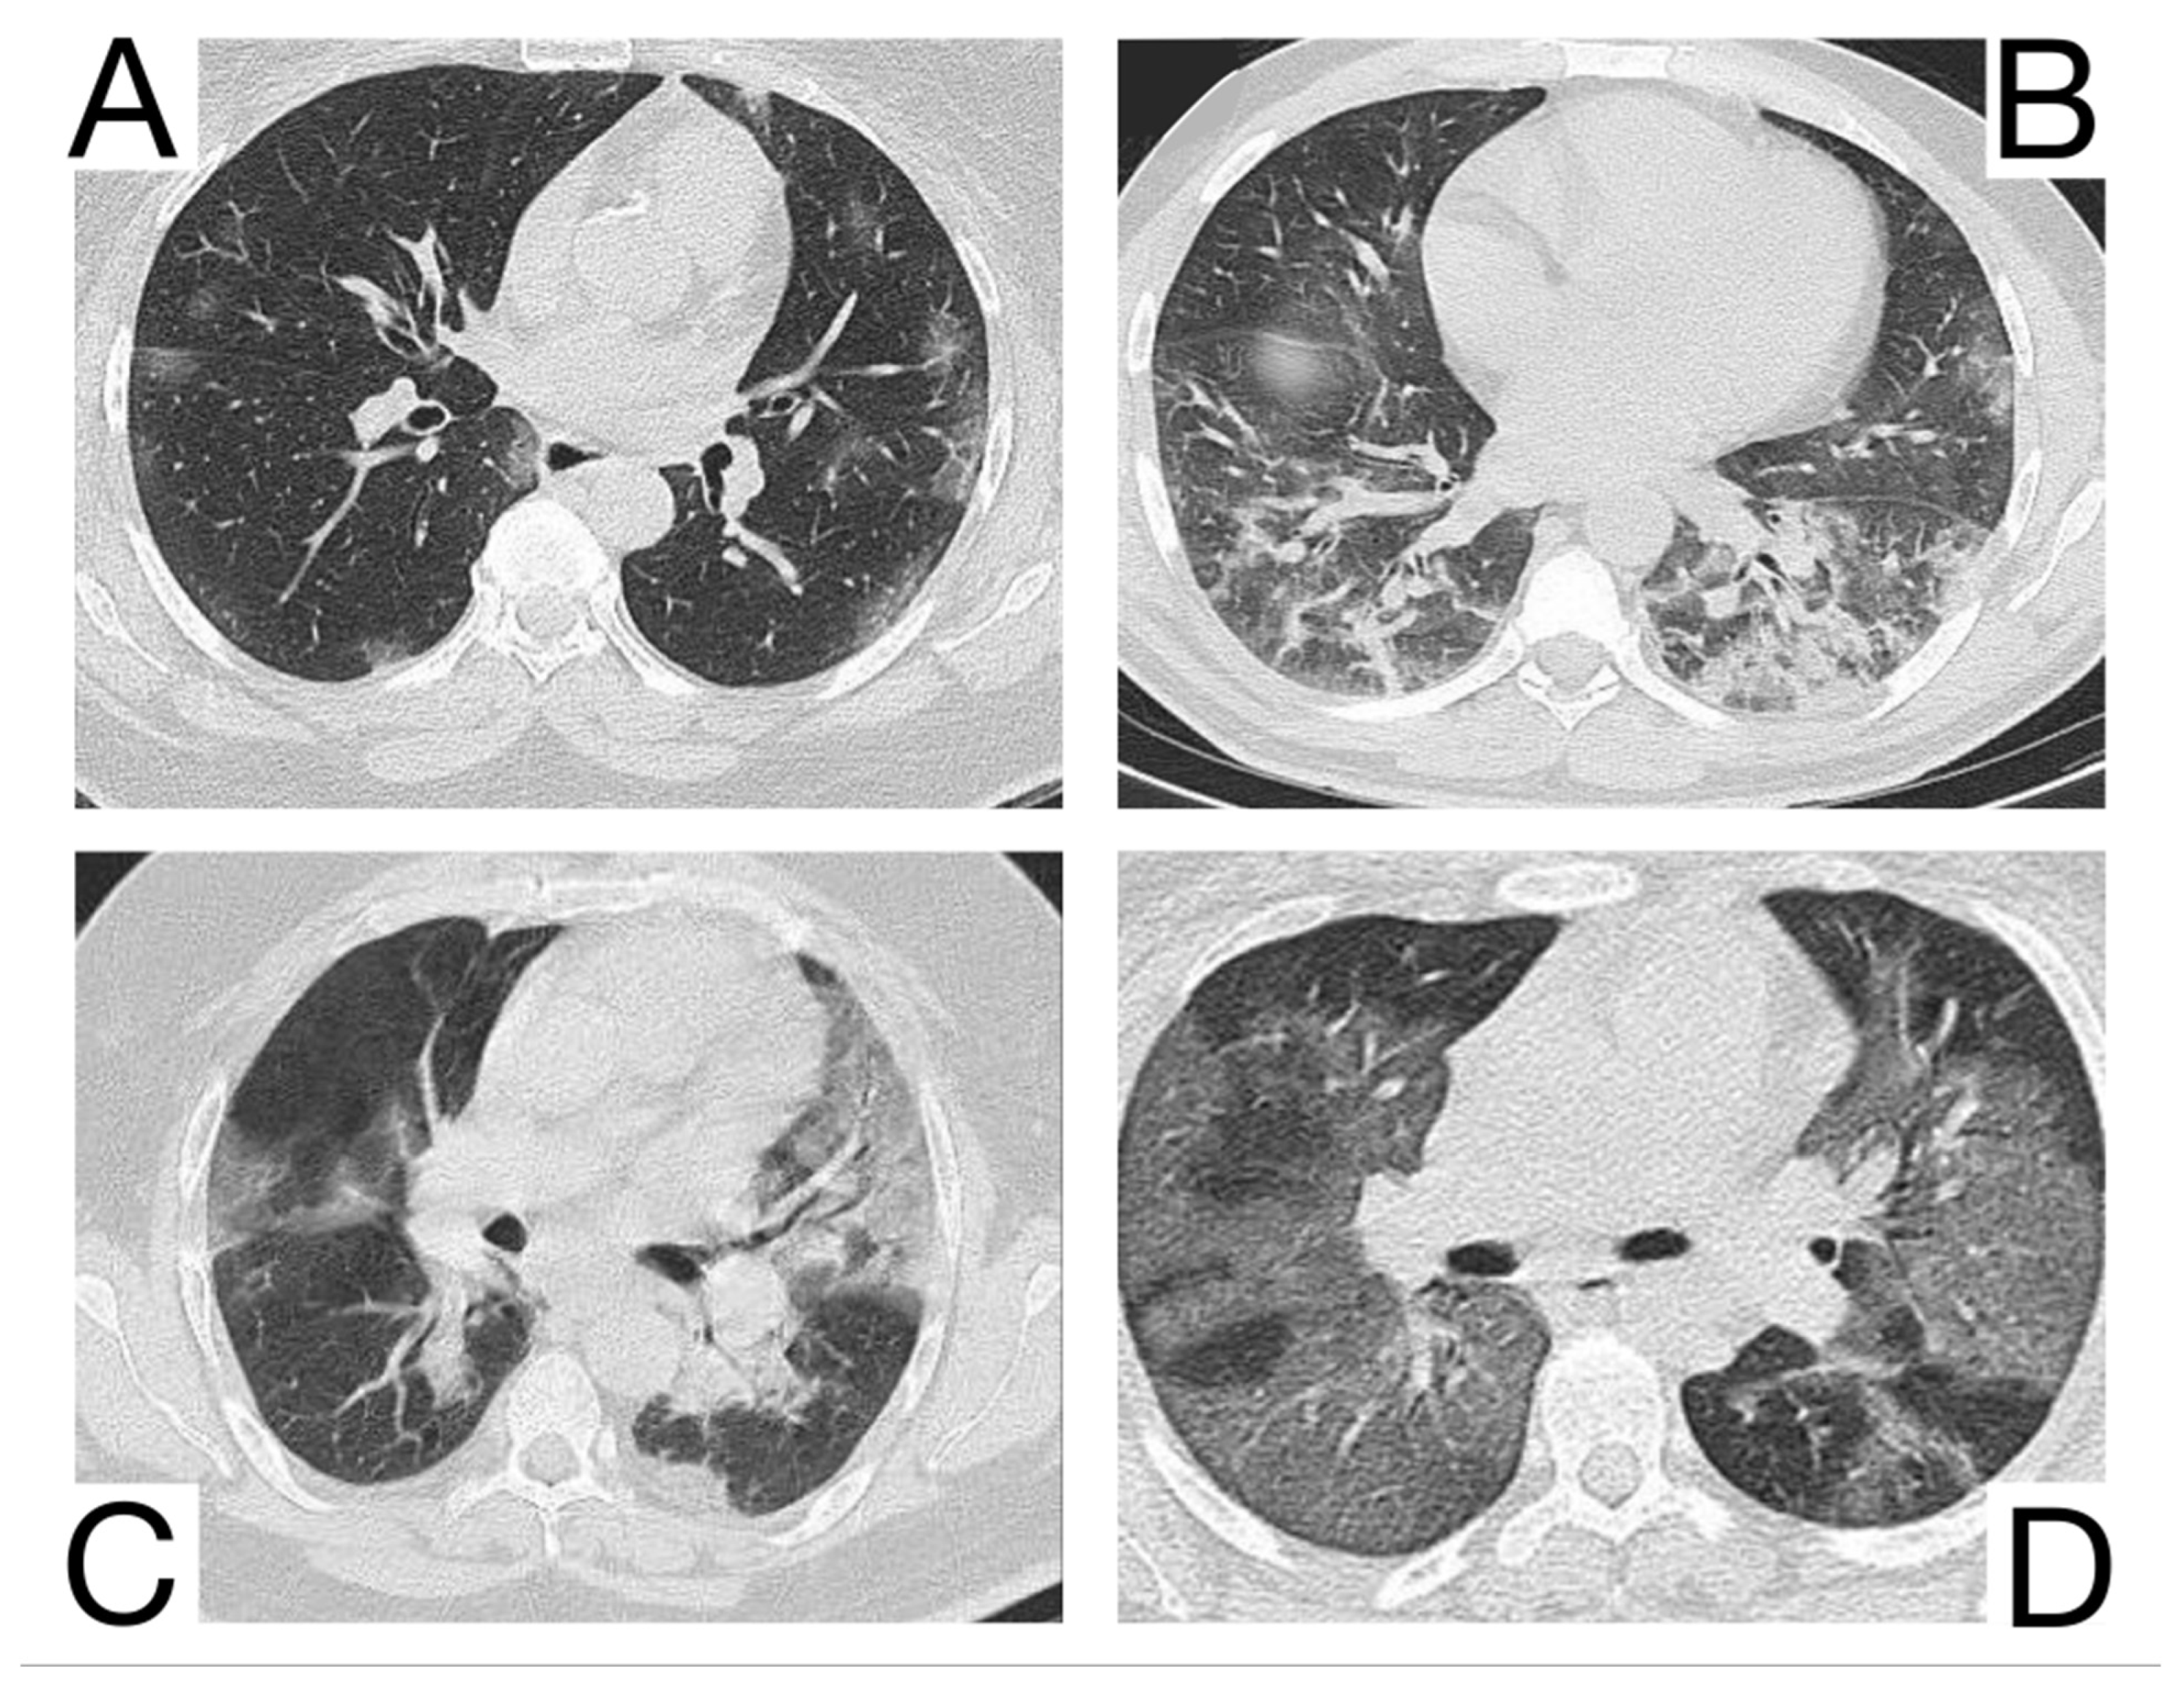

10.12. Differential Diagnosis between COVID-19 Pneumonia and Idiopathic Interstitial Pneumonia (IIP)

COVID-19 pneumonia and IIP represent complex pulmonary pathologies, and the differential diagnosis is frequently challenging.

Idiopathic interstitial types of pneumonia and COVID-19 pneumonia are different entities but share some similar radiological features.

Yet, a discordance between the patients’ anamnesis and the imaging should suggest a possible differential diagnosis [,]. Comparison with previous CT scans is crucial to identify possible chronic or long-standing radiological findings of IIP. In general, the presence of typical and/or additional radiological changes that are less frequent or rare in COVID-19 pneumonia is found in IIP (Figure 13A,B) [,]: the migration of condensation foci (organizing pneumonia); preferential involvement of the lobular periphery, resulting in a “peri-lobular pattern” (pneumonia in organization); ground glass opacities during disease exacerbation; relative reduction of the subpleural lung tissue (nonspecific interstitial pneumonitis, organizing pneumonitis); predominance in the upper fields (bronchiolitis associated with interstitial lung disease, lymphoid interstitial pneumonia, pleuropulmonary fibroelastosis) []; apicobasal gradient and heterogeneous lung involvement (idiopathic pulmonary fibrosis); clear demarcation between the healthy lung parenchyma and the affected parenchyma (idiopathic pulmonary fibrosis) []; the coexistence of other radiological findings such as centrolobular nodules (bronchiolitis associated with interstitial lung disease, organizing pneumonia) and thin-walled cysts (interstitial lymphoid pneumonia) []; the presence of fibrosis that can be appreciated as parenchymal distortion, bronchial traction, and/or honeycombing (idiopathic pulmonary fibrosis, nonspecific interstitial pneumonitis); pleural thickening (pleuropulmonary fibroelastosis); pleural effusions (exudative acute interstitial pneumonia, organizing pneumonia).

Figure 13. Idiopathic interstitial pneumonia (A,B). Bilateral septal thickening and honeycombing with more severe involvement toward the lung bases. Note. Case courtesy of Dr. Hani Makky Al Salam, Radiopaedia.org, rID: 41974.

The differential diagnosis of COVID-19 pneumonia with IIP is challenging because these entities may share common radiological aspects. Therefore, a multidisciplinary approach is crucial to arrive at a final and correct diagnosis [,].